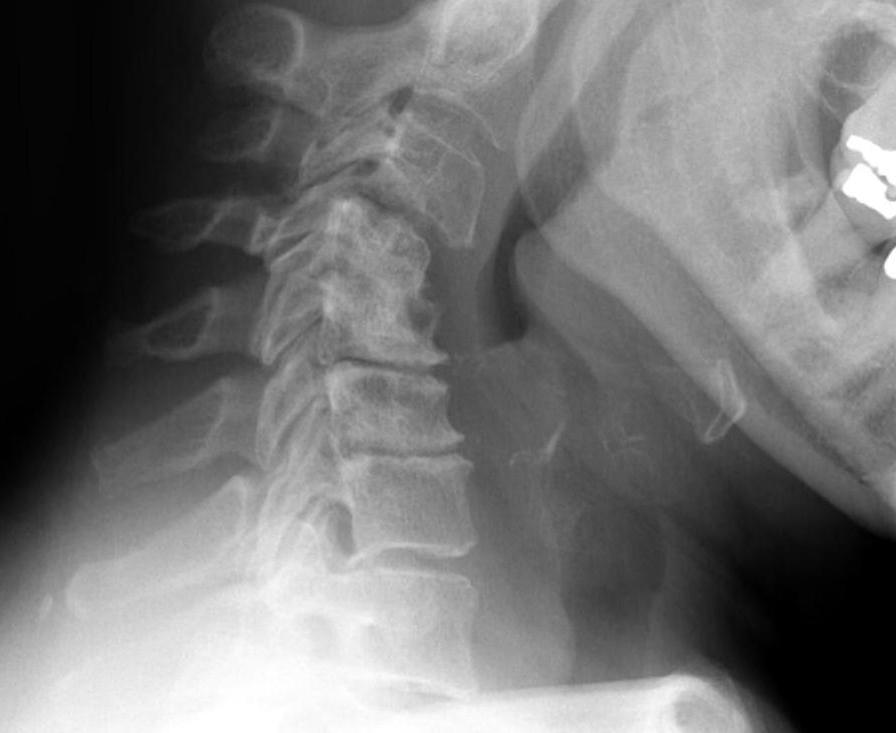

Xray

Atlanto-dens interval (ADI)

Space available for Cord (SAC) / posterior atlanto-dens interval (PADI)

1. AADI (anterior atlantodental interval) > 3 mm

2. Instabilty

A. Instability : > 3 mm difference in flexion / extension views

B. Severe instability: > 7 mm difference

Instability 3 mm

Severe instability

3. PADI (posterior atlantodental interval / SAC (space available for cord))

- > 14 mm 94% predictive no neural deficit

- < 14 mm 97% predictive neural compression